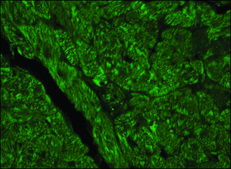

indirect immunofluorescence: 15-30 μg/mL using acetone-fixed frozen sections of rat or human heart, western blot: 2.5-5 μg/mL using whole extracts of cultured mouse NIH3T3 cells and human hepatoma HepG2 cells